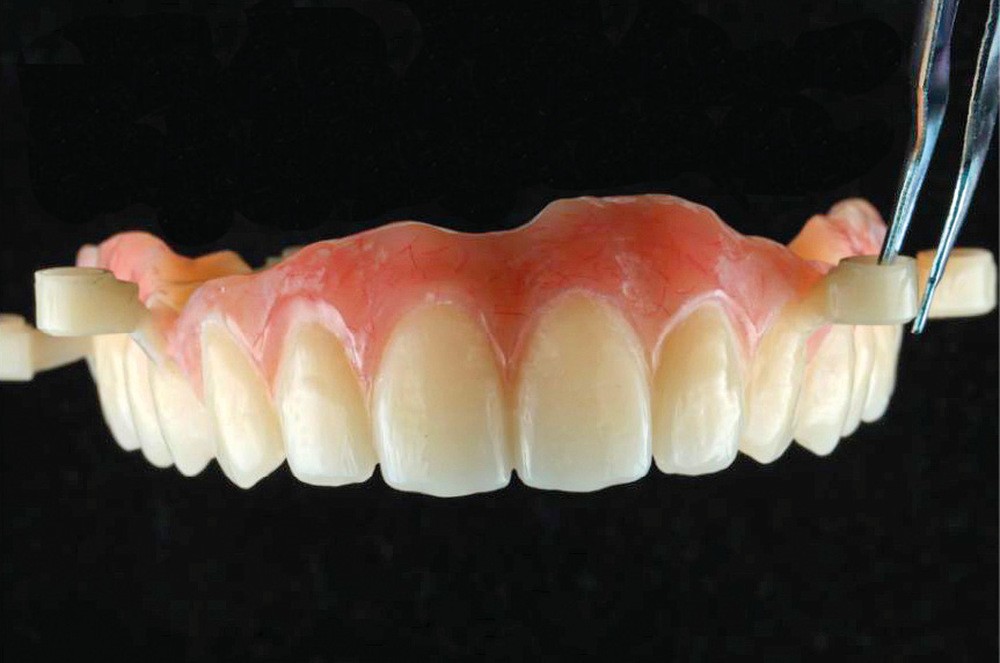

Le matching classique avec les fichiers STL et Dicom fut imprécis. La technique inspirée du « double scan » à l’aide de points radio-opaques sur la PAP provisoire maxillaire et d’un double CBCT a permis d’obtenir un matching extrêmement précis et la conception d’un projet prothétique numérique (Nemotec) associé à un Smile design (fig. 2). La modélisation 3D et le CBCT ont permis d’élaborer une planification implantaire, des guides à étages et un bridge complet provisoire en PMMA usiné (Biotech). La planification de 8 implants au niveau des 7/6/4/3 en fonction du volume osseux disponible et du projet prothétique virtuel a confirmé la possibilité de proposer un traitement sans greffe antérieure (fig. 3).

Après une extraction atraumatique des dents résiduelles, nous passons au 3e étage qui est le guide de forage stéréolithographique. La séquence de chirurgie Full guided est passée et les implants ont été torqués entre 40 et 50N.cm2 (fig. 6, 7, 8). Cette stabilité primaire dans les sites d’extraction et des sites greffés a permis la mise en charge immédiate du bridge complet provisoire. Des études cliniques [3, 4, 5] ont montré que la mise en charge immédiate dans les sinus greffés ne pose aucune contre-indication. Le 4e étage est donc celui du bridge provisoire transvissé à l’étage de base et solidarisé en bouche par l’intermédiaire de cylindres provisoires sur piliers MUA, avec une colle duale (GC-LinkForce). L’espace entre les implants et l’alvéole a été comblé par une xénogreffe (Bio-Oss Geistlich). Les profils d’émergence sont travaillés et parfaitement polis. Enfin, le bridge est mis en place, torqué à 20.cm2, équilibré et les consignes postopératoires ont été rappelées à la patiente (fig. 9 et 10).